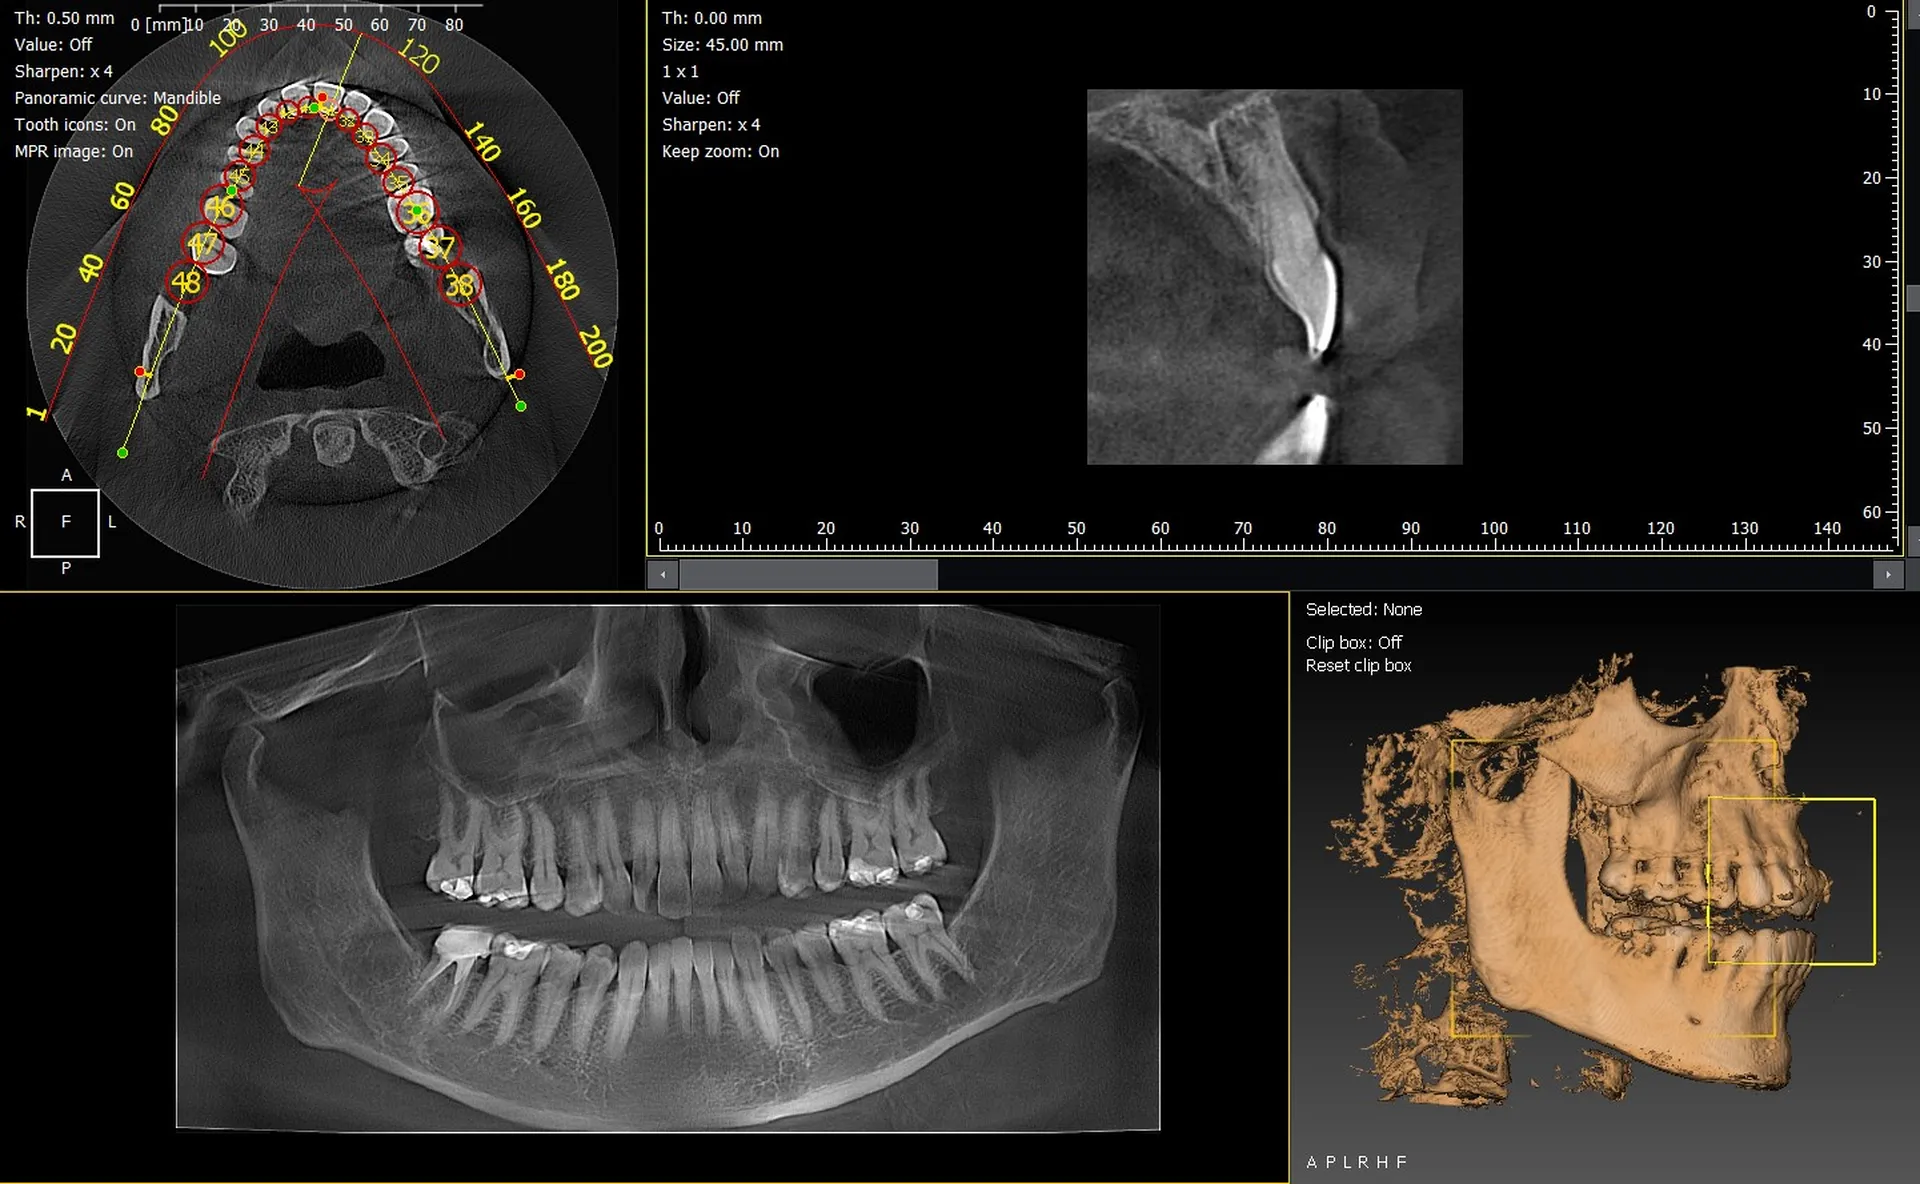

Les cabinets dentaires de Draguignan et du département du Var (83) améliorent leur infrastructure d’imagerie en intégrant des panoramiques 3D performants. Les systèmes CBCT 3D VistaVox de Dürr Dental et l’Owandy I-Max 3D comptent parmi les équipements les plus avancés, offrant une précision d’image exceptionnelle pour un diagnostic fiable.

VistaVox 3D : précision et volume optimisé

Le Dürr Dental VistaVox offre :

• un volume d’imagerie adapté à l’arcade,

• une haute résolution pour implantologie et endodontie,

• une dose réduite,

• un positionnement patient simplifié.

Il convient parfaitement aux cabinets du Var ayant une forte activité implantologique.

Owandy I-Max 3D : compact, polyvalent et simple d’utilisation

L’Owandy I-Max séduit grâce à :

• son format mural gain de place,

• ses protocoles rapides,

• son excellente qualité d’image,

• son interface intuitive.

Un choix idéal pour les cabinets urbains de Draguignan souhaitant optimiser l’espace.